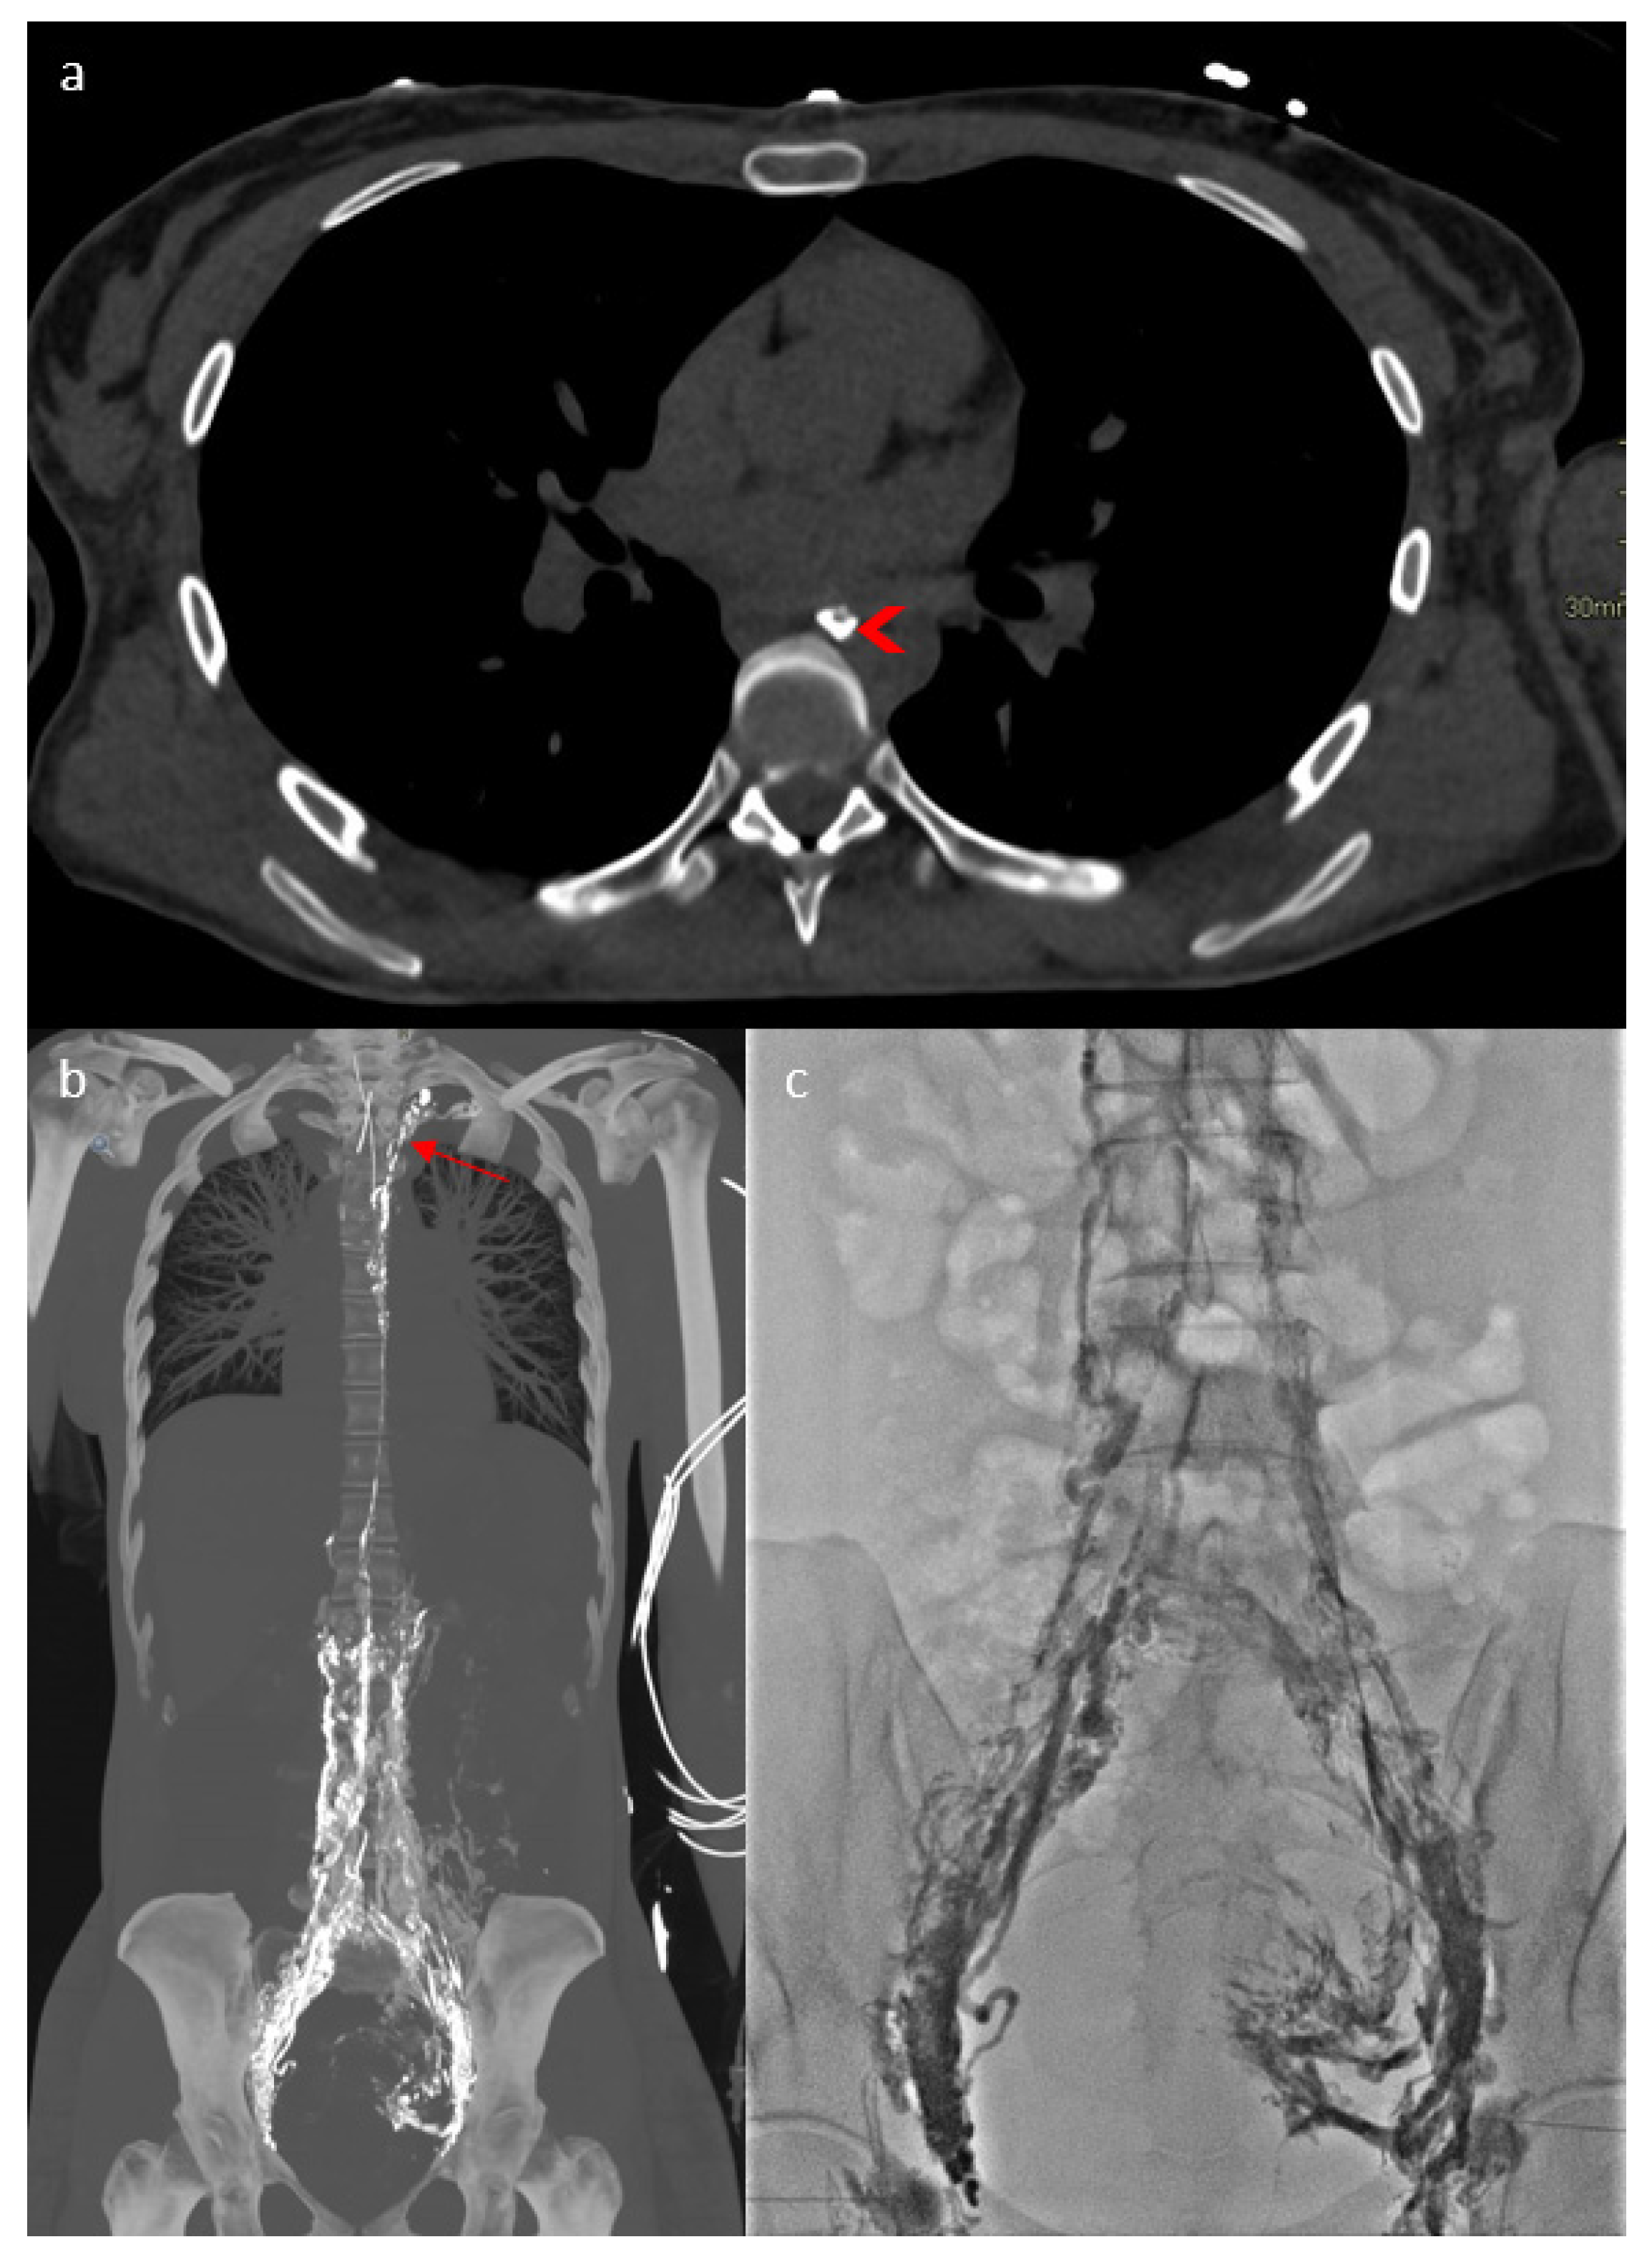

2. Case Report

3.1. Case Discussion and Physiopathological Hypothesis

3.2.3. Imaging